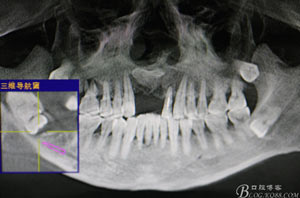

圖2.術(shù)前的CBC影像T檢查:48低位導(dǎo)致,近中牙尖緊鄰下頜神經(jīng)管。

圖3.其他方向的影像檢查:48近中牙冠與下頜管之間無(wú)骨壁相隔。

圖4.總體的CBCT影像: